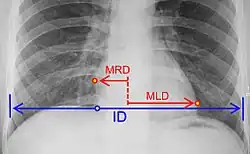

Cardiothoracic ratio =

where:[29]

MRD = greatest perpendicular diameter from midline to right heart border

MLD = greatest perpendicular diameter from midline to left heart border

ID = internal diameter of chest at level of right hemidiaphragm

• Chest X-ray: X-ray images help to visualize the condition of the lungs and heart. If the heart is enlarged on an X-ray, other tests will usually be needed to find the cause. A useful measurement on X-ray is the cardio-thoracic ratio, which is the transverse diameter of the heart, compared with that of the thoracic cage.[30] These diameters are taken from PA chest x-rays using the widest point of the chest and measuring as far as the lung pleura, rather than lateral skin margins. If the ratio is greater than 50%, pathology is suspected.[31] The measurement was first proposed in 1919 to screen military recruits. A newer approach to using these x-rays for evaluating heart health takes the ratio of heart area to chest area and has been called the two-dimensional cardiothoracic ratio.[32]